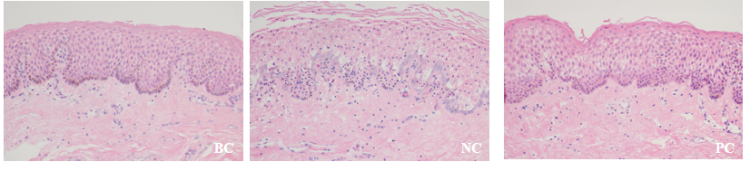

图1 组织形态染色典型图

1、组织形态

皮肤外植体获取与消毒——皮肤外植体无菌培养——紫外照射及加药处理(空白对照组:不处理;模型对照组:紫外照射;样品组:紫外照射+待测样品处理)——组织固定——石蜡包埋——切片——H&E染色、Masson染色——显微镜拍照及分析